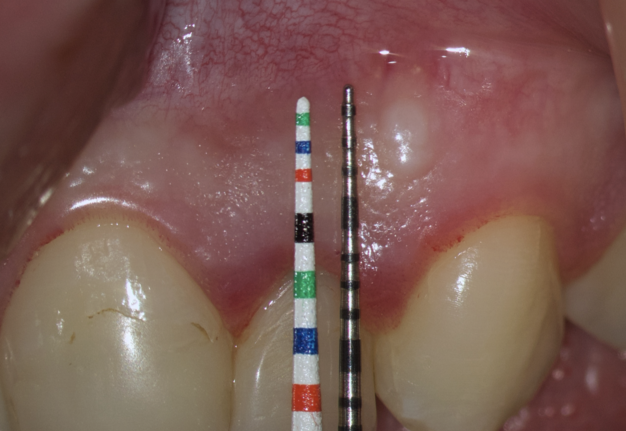

The submarginal flap is only to be used, when there is a broad zone of attached gingiva with a minimum of 2 mm [9]. The width of the attached gingiva is then calculated on the basis of the distance from the base of the sulcus to the linea girlandiformis (mucogingival junction) [6]. Consequently, the incision must be placed at least 2 mm from the depth of the gingival sulcus. Extensive periodontal probing should be done to establish the depth of the gingival sulcus before the incision is made [10]. Periodontal probing should be conducted not only around the causative tooth but also in the adjacent teeth.

We transfer this distance is transferred to a metal probe and fixed with an endodontic stopper. Next, we take a plastic probe and substitute it near the zenith of a tooth on which the intervention will be performed at a mark of 6 mm (3 mm must be retreated to perform a submarginal incision and another 3 mm is needed for the formed flap to overlap healthy bone tissue) (Fig 8).